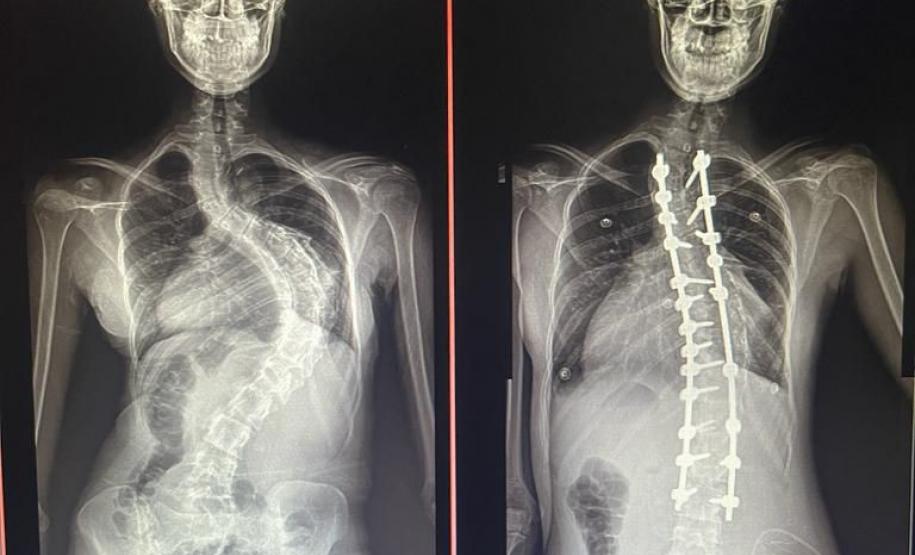

Outro tipo de escoliose é a causada por doenças neuromusculares, como paralisia cerebral, mielomeningocele, distrofia muscular, atrofia muscular espinhal, entre outras. No caso do Lucas Batista da Paixão, de 18 anos, a paralisia cerebral que teve ao nascer foi o que desencadeou a condição.

Com curvatura acima dos 100 graus, desconfortos respiratórios como falta de ar e asma, a posição do adolescente na cadeira de rodas estava bem limitada. Para a mãe de Lucas, Daniele de Oliveira Batista, a cirurgia foi fundamental para melhorar a autonomia e qualidade de vida do filho.

“Foi um longo processo até chegar aqui no CHT, esperávamos por essa cirurgia há mais de dois anos e, depois de tantas dificuldades, hoje conseguimos fazer um passeio sem que ele reclame de dor. Ele também já consegue ficar em muitas outras posições que antes eram desconfortáveis e geravam muita dor. Só temos a agradecer a toda equipe médica pelos cuidados e ótimo atendimento prestado ao meu filho”, disse.